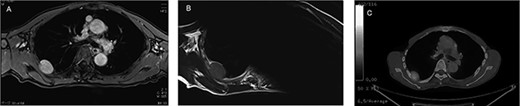

An asymptomatic 79-year-old male who was diagnosed with a chest wall tumor, which had been detected by an X-ray of a health examination, presented to our hospital for surgical intervention. He had no relevant past medical history, including malignant neoplasm or radiation therapy. No mass was palpable. The chest X-ray revealed a tumor shadow of 3 cm in diameter in the right upper lung field (Fig. 1). Chest contrast computed tomography (CT) revealed a well-circumscribed tumor shadow measuring 37 × 27 mm in the posterolateral region of the right sixth intercostal space, the size of which had increased 1.5 times in the previous 3 months (Fig. 2). Thoracic magnetic resonance imaging (MRI) revealed a solid tumor that was enhanced by gadolinium on T1-weighted imaging (T1WI). T2-weighted imaging (T2WI) showed a homogeneous mass with iso-intensity. The tumor was inhomogeneous while demonstrating a maximum standardized uptake value (SUV) of the [18F]-2-deoxy-D-glucose (FDG) uptake under positron emission tomography (PET), with a range of 3.4–4.1 (Fig. 3). There was no significant uptake at other sites, including the mediastinal lymph nodes. No tumor-markers (CEA, proGRP and CYFRA) were detected in a laboratory analysis. Based on these examinations, we suspected a neurogenic tumor, especially schwannoma, and we opted for surgical resection. Considering the fact that ~10% of neurogenic tumors are malignant and the FDG uptake was heterogeneous, we planned to perform an intraoperative frozen section examination. We first performed tumor resection. The operation was performed in the left lateral position under general anesthesia. A 30° viewing angle thoracoscope was set at the middle axillary line of the seventh intercostal space. The tumor was smooth, slightly solid and covered with pleura (Fig. 4). We added a 4-cm incision just above the tumor, while verifying its location through the thoracoscope, and easily removed it from the chest wall. The tumor was diagnosed as sarcoma based on the frozen section examination. Therefore, we added removal of a portion of the sixth and seventh right rib. We excised the chest wall with a 2-cm margin from the lesion, confirming an adequate length through the thoracoscope. Chest wall reconstruction was performed with DUALMESH® (Gore, Flagstaff, AZ). On the cut section, the tumor appeared as solid, smooth-surfaced and encapsulated whitish mass of 3.7 × 2.7 cm in size. Upon microscopic examination, the tumor was composed of fascicles of highly atypical spindle cells mitotic figures exceeding 15 per 10 high-power fields. Immunohistochemistry was positive for αSMA (Fig. 5), desmin and caldesmon and was negative for S-100 protein (data not shown). All margins were negative, and no invasion to the peripheral organs was seen. We concluded that the tumor was leiomyosarcoma of the chest wall. He was discharged on post-operative day 10 without any complications. Since we considered that curative resection had been achieved, no adjuvant therapy was performed. He is still being followed up; however, liver and multiple lung metastases were detected at 5 years after surgery.

Preoperative MRI and PET-CT: (A) contrast-enhanced T1WI: hyper-intense; (B) T2WI: iso-intense; (C) PET-CT: SUVmax 3.4–4.1.